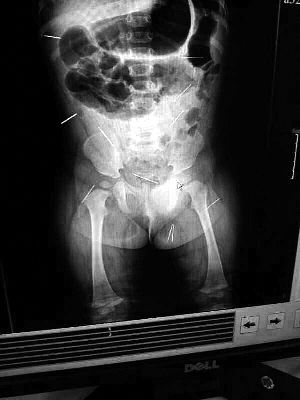

山東聊城11個(gè)月女?huà)胼孑妫ɑ┮伤票蝗艘?2根鋼針插滿(mǎn)臀部、腹腔等部位,昨天在兒童醫(yī)院會(huì)診后,醫(yī)生稱(chēng)3根針靠近胸腔最危險(xiǎn),首批先行取出,預(yù)計(jì)將在下周二手術(shù)。孩子父母稱(chēng)孩子一直由家人照顧,自家與他人并無(wú)冤怨。山東警方表示正在偵破中,不便透露案情。

“要不是當(dāng)初那幾個(gè)紅點(diǎn),可能到現(xiàn)在我們還不知道孩子身體里有鋼針!”昨天,在兒童醫(yī)院住院處,萱萱爸爸范先生稱(chēng),日前原本很愛(ài)笑的萱萱突然變得有些焦躁,一抱起來(lái)就哭,孩子母親偶然間在萱萱屁股上發(fā)現(xiàn)了幾個(gè)小紅點(diǎn)兒,原以為是蚊蟲(chóng)叮咬,就醫(yī)結(jié)果卻讓人不寒而栗?!搬t(yī)院拍出的片子上,萱萱的體內(nèi)有12根鋼針,插滿(mǎn)臀部、腹腔、骨盆等各個(gè)部位?!狈断壬榻B,因?yàn)殇撫樢焉钊塍w內(nèi),要是孩子不哭鬧,他們很難發(fā)現(xiàn)。

北京晨報(bào)記者了解到,目前體內(nèi)的12根鋼針多分布在孩子的臀部,一根在腹部,其余3根在胸腔附近,其中一根很接近心臟?!耙?yàn)楹⒆犹?,醫(yī)生們害怕取針的時(shí)候?qū)λ斐蓚?,在胸腔附近?針可能會(huì)威脅她的生命”。